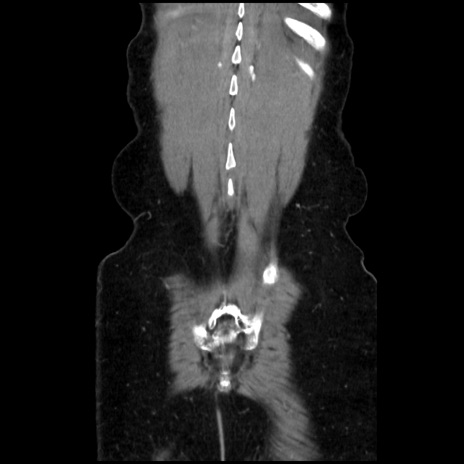

症例32(冠状断像)

矢状断像

【症例】40歳代 女性

【主訴】上腹部痛、嘔気・嘔吐

【現病歴】約9時間前頃から急に上腹部痛、嘔気、嘔吐が出現。改善しないため救急要請。

【既往歴】子宮頚癌(広汎子宮全摘術、放射線療法)、腸閉塞

【身体所見】腹部:平坦、軟、腸雑音亢進、上腹部を中心に腹部全体に圧痛あり。

【データ】WBC 8400、CRP 0.03